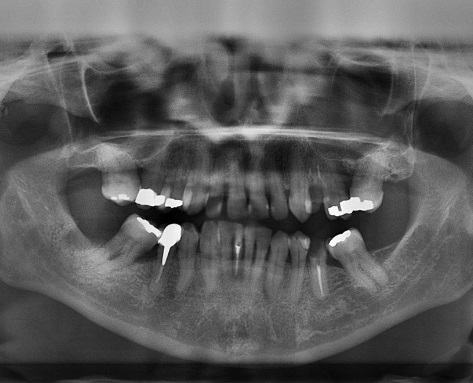

Izpostavljenost organizma živemu srebru že dolgo velja za škodljivo za zdravje ljudi, kar so pokazale že številne raziskave. Živo srebro se med drugim uporablja za zobne zalivke, tako imenovane klasične amalgamske zalivke. Amalgami so zlitine živega srebra in drugih kovin, živo srebro se uporablja zaradi njegovih vezivnih lastnosti in obstojnosti takšnih zalivk.

Raziskava, ki jo je izvedla skupina strokovnjakov z ameriške univerze Georgia, je pokazala, da je raven živega srebra v krvi ljudi, ki imajo v ustih osem amalgamskih zalivk, dvakrat višja kot pri tistih brez zalivk.